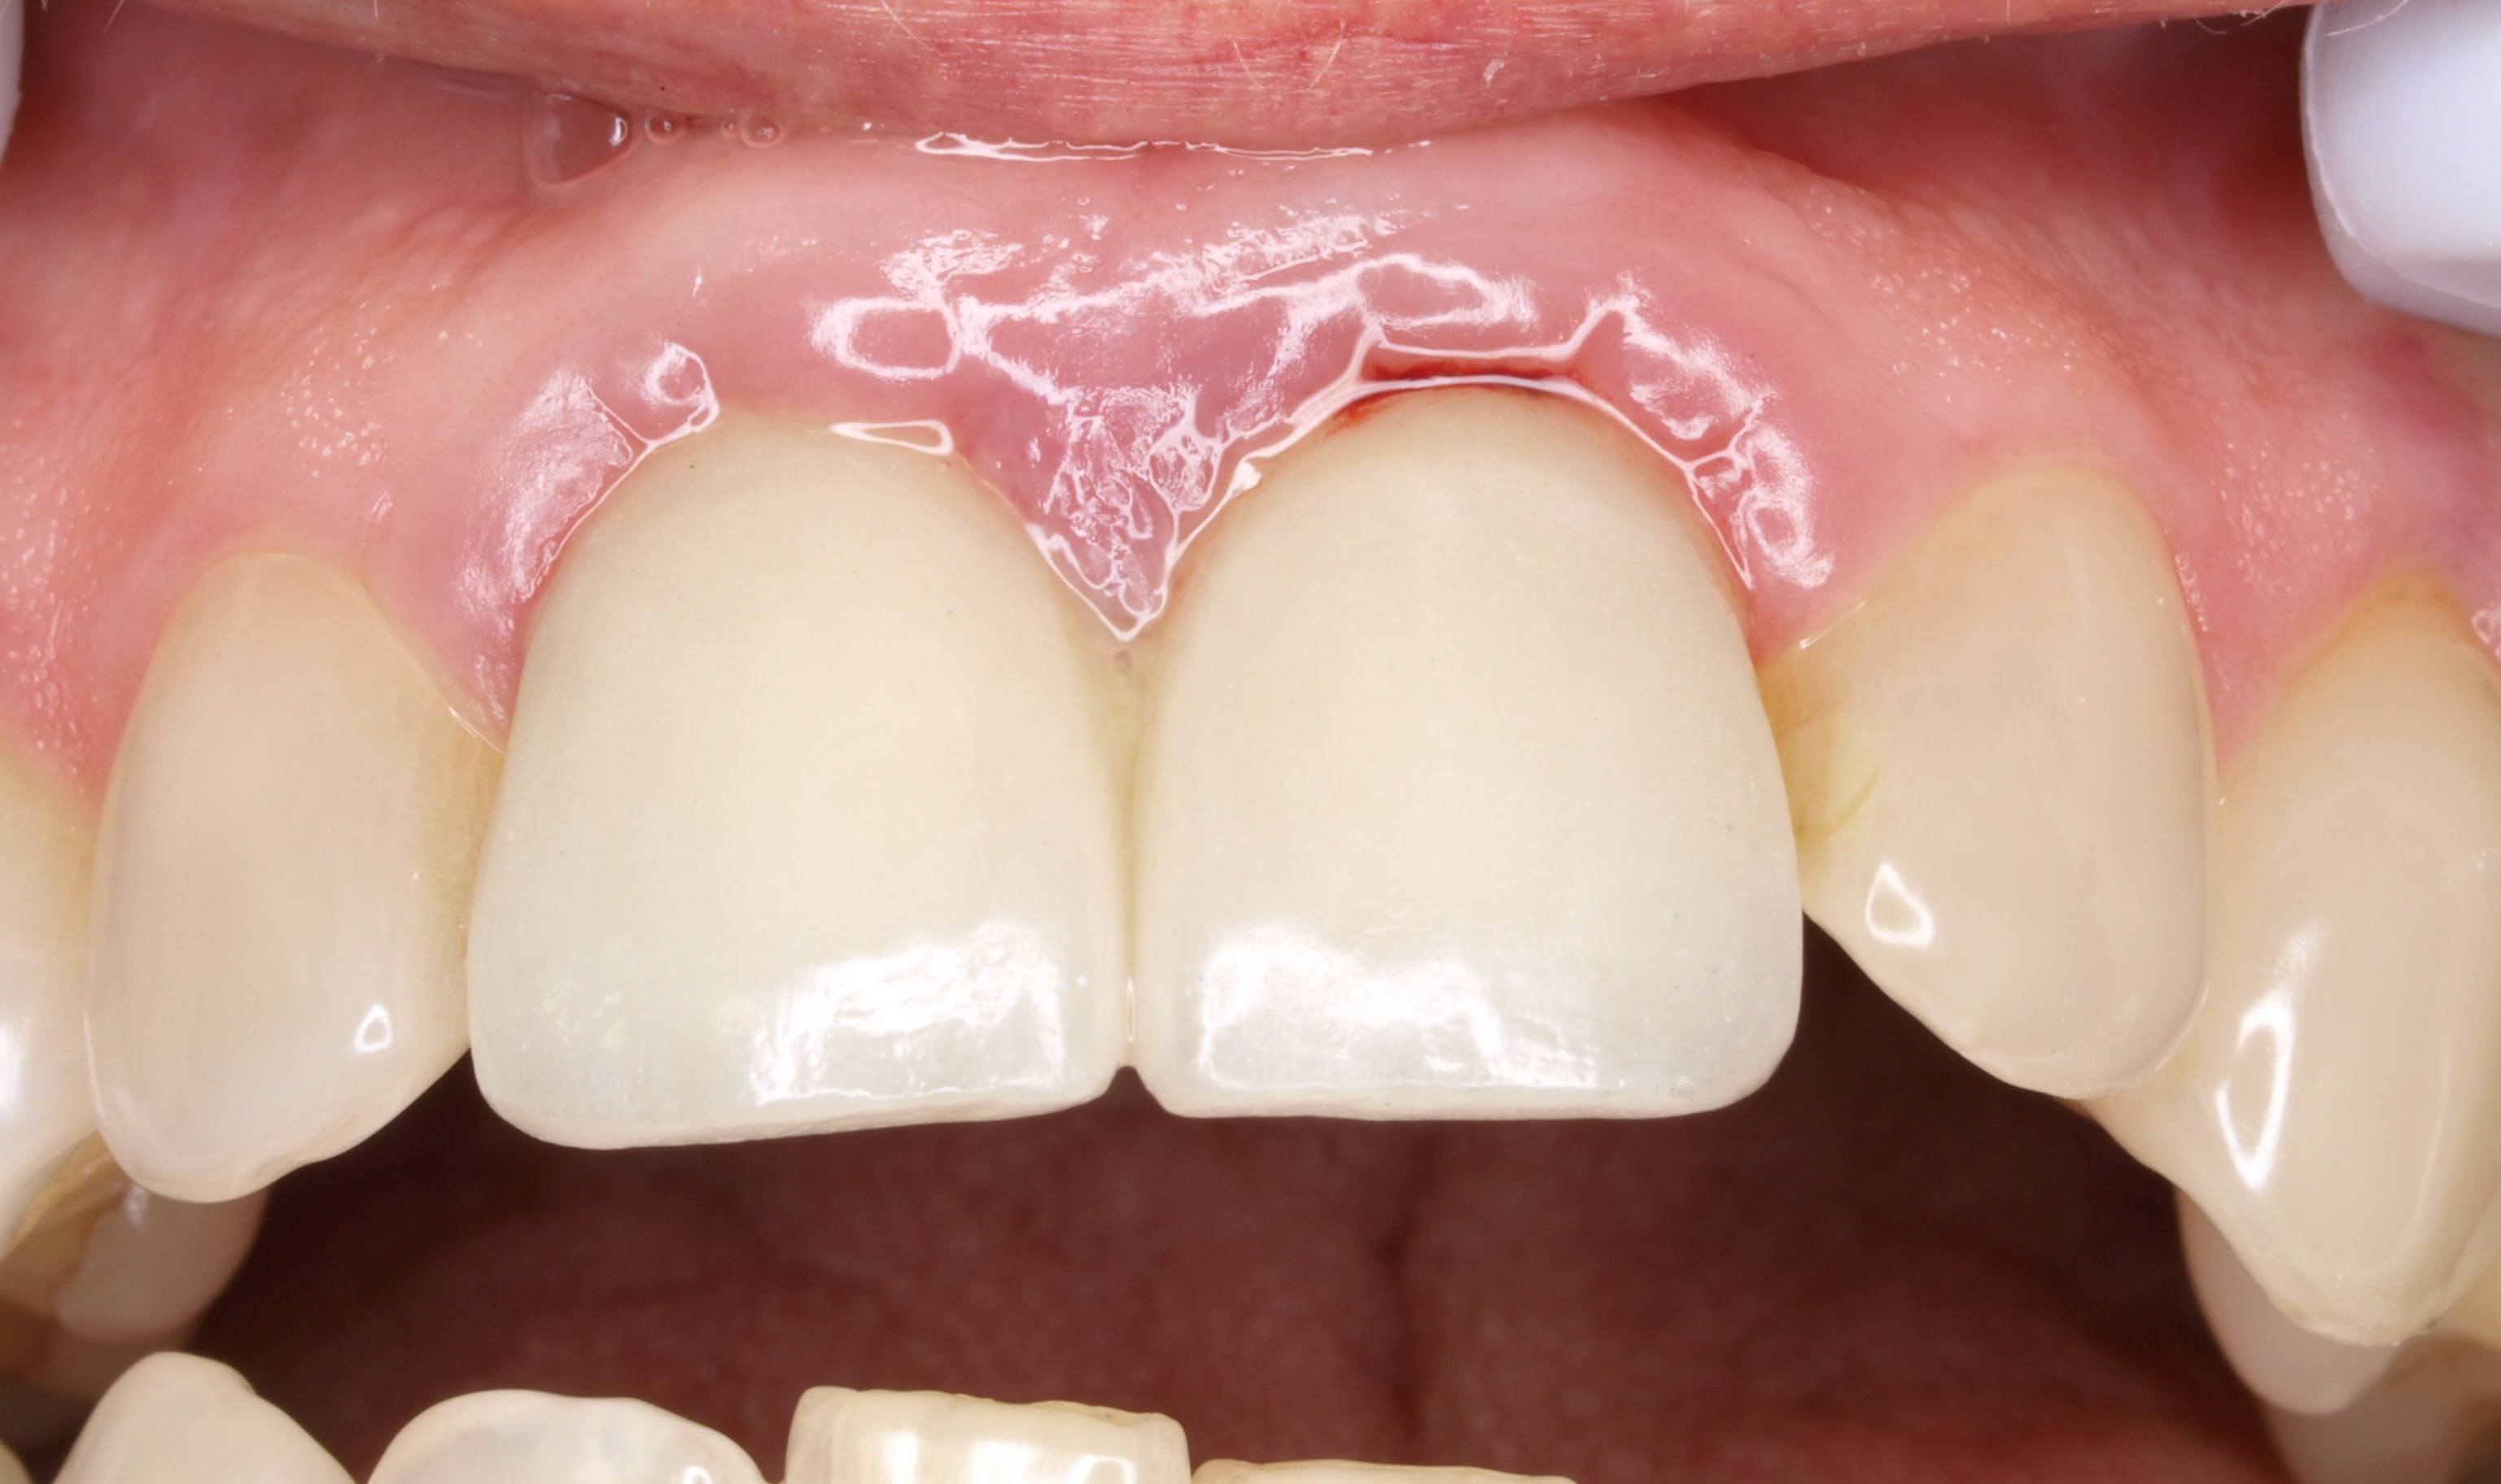

le meme genre de cas avant et apres le jour de la pose

plus tard la papille s'est recrée .

Oui on voit que c'est trop agressif au niveau du sulcus !!